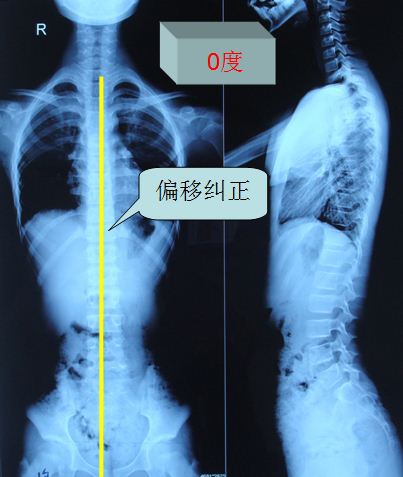

腰椎管狭窄症并脊柱侧弯的治疗前后比较 - 好大夫在线

图片尺寸960x1280